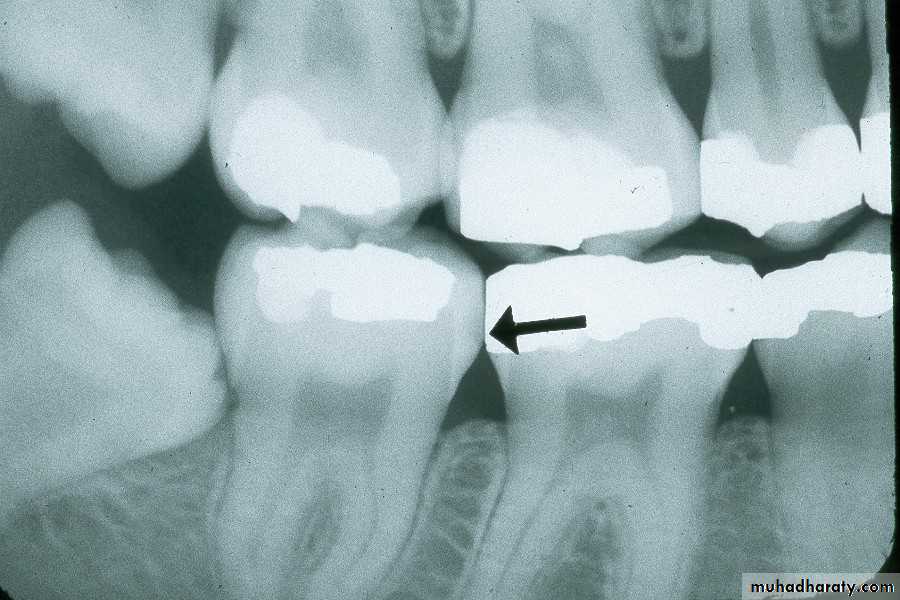

Buccal and Lingual Caries

Buccal caries seen as a small, circular radiolucency on

Recurrent caries on upper first premolar